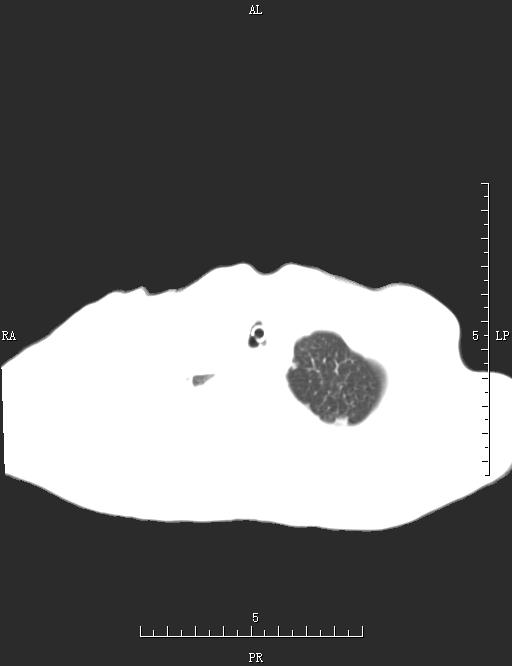

CT52438:胸部CT

男,54岁,咳嗽、咳痰、憋气10天。

双侧胸腔积液以右侧为著并右肺压迫性膨胀不全。

左肺少许炎症。